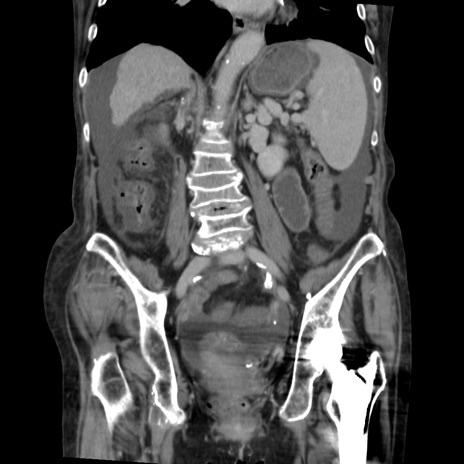

症例31(冠状断像)

【症例】80歳代 女性

【主訴】腹部膨満感

【現病歴】他院にて肝硬変にてフォロー中。1週間前から便秘、腹部膨満感、臍部腫瘤あり受診となる。

【既往歴】肝硬変

【身体所見】腹部膨隆あり、皮膚変化なし、疼痛なし。

【データ】WBC 4600、CRP 0.25